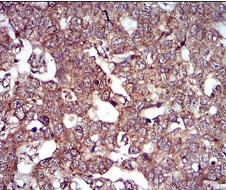

IHC    1/200 - 1/1000